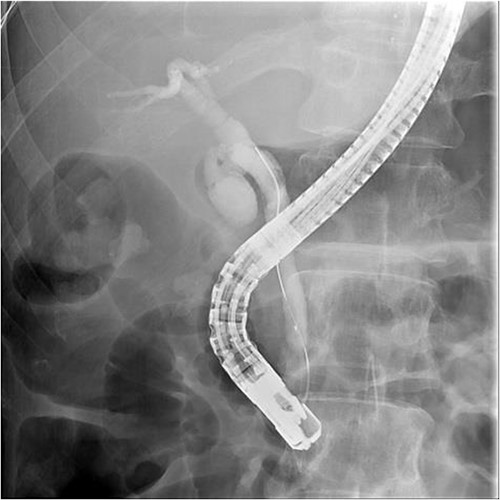

ERCP with a sphincterotomy was performed. After several attempts of wire-guided cannulation, successful CBD cannulation was achieved and confirmed by the cholangiography. Due to distal CBD stricture, we then used endoscopic balloon dilation repetitive of trying, we assumed deep cannulation to pass through the CBD stone was achieved because the guide wire advanced smoothly (Fig. 2).

Successful wireguide CBD cannulation to pass through the opacified CBD stone following by cholangiography.